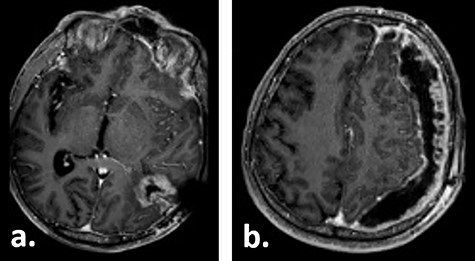

Ten weeks postoperatively, the patient complained of vertigo and a self-limiting episode of right-sided visual field restriction and neglect. Subsequently, oral cortisone therapy was started again, which lead to the relief of these symptoms. The MRI showed a new contrast enhancement around the resection cavity, possibly treatment-related after radiochemotherapy, as well as a 14-mm-thick, left-sided subdural fluid collection causing a midline shift of 6 mm, which was interpreted as a subdural hygroma or hematoma (Fig. 2). The latter was slightly progressive on a CT scan 1 week later, and surgical evacuation through a burr hole was indicated. Intraoperatively, it presented as a slightly xanthochrome, slightly pressurized subdural hygroma. No pathological alterations of the dura were revealed during this procedure. Postoperatively, the subdural hygroma was incompletely regressive and began to grow again as was seen on the CT images 3 weeks after the surgery. This finding was considered to be related to post-radiation changes. The patient stayed asymptomatic and received two cycles of adjuvant chemotherapy with temozolomide 150 mg/m2 body surface area and 200 mg/m2 body surface, respectively.

Gadolinium-enhanced T1-weighted axial MRI of the patient 10 weeks after tumour resection demonstrating the resection cavity (a) and new subdural fluid collection (b).